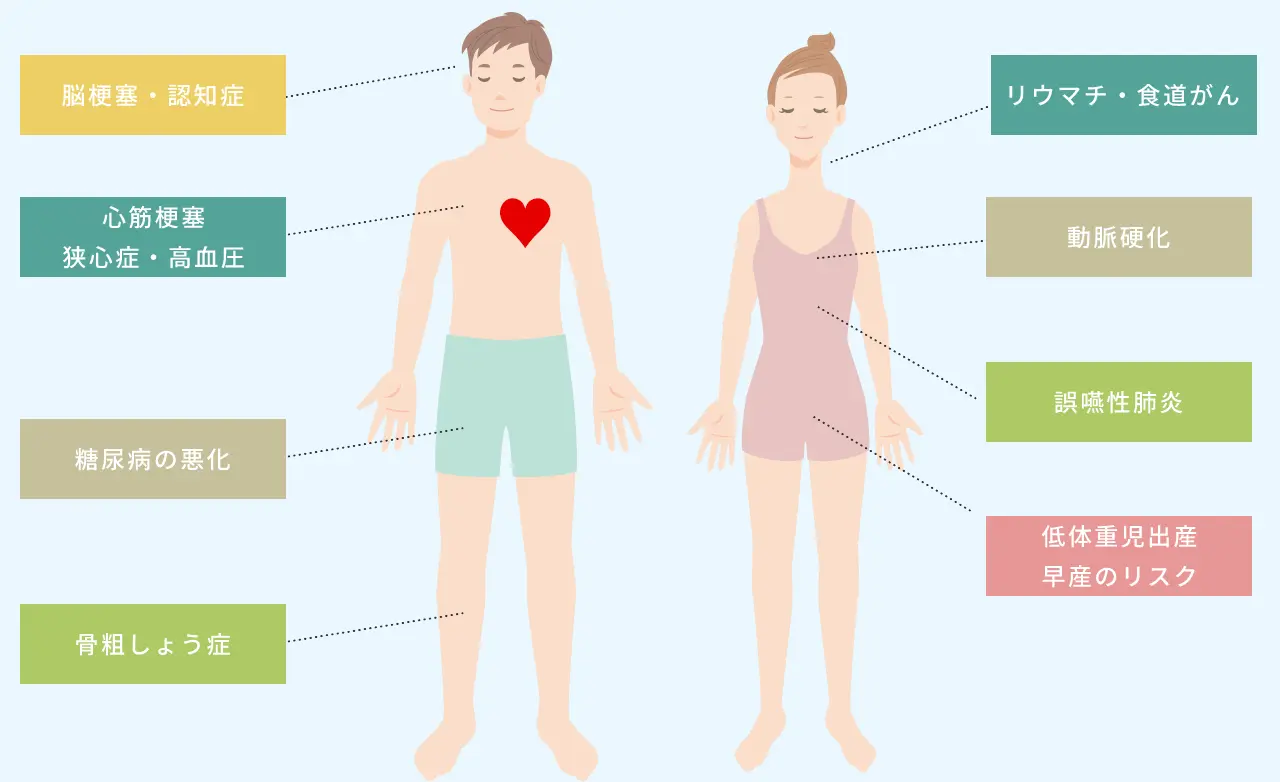

歯周病と全身疾患の関係

歯周病は全身の健康に

影響を及ぼすことがあります

歯周病は、歯やお口だけでなく、全身に影響を及ぼす可能性がある疾患です。歯周病が進行すると、歯ぐきからの出血や炎症を引き起こします。 これらが歯ぐきの毛細血管から全身に巡ると、脳梗塞や認知症、狭心症、高血圧、糖尿病の悪化、早産リスクなどの異変を起こすことがあります。 歯周病の早期発見・治療は全身の健康を守ることにつながります。定期的に歯科医院で検診を行い、歯周病によるトラブルを予防しましょう。